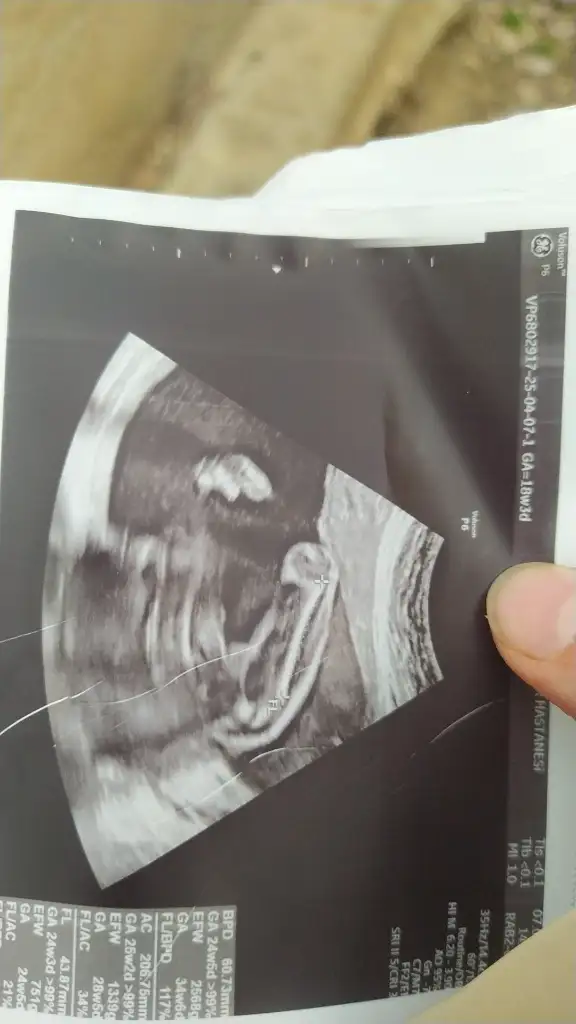

Bence de pipi o zaten erkek belliEki Görüntüle 3572989 Tahmini yapabilir misiniz

bilmiyorum ilk hamileliğim hiç bir bilgim yok sizce erkek mıPipi değil mi o

İki bacağın ortasında o şey pipi miiii yaaaa cildircammmmEki Görüntüle 3572989 Tahmini yapabilir misiniz

Kaç haftalıksiniz acaba

12Kaç haftalıksiniz acaba

Pipi değil mi o

Kizlar peki sizce bu bebişin cinsiyeti nedirErkek olabilir eğer o kordon değilse

sanki bu da pipi emin olamadım ama pipiye benziyoKizlar peki sizce bu bebişin cinsiyeti nedir